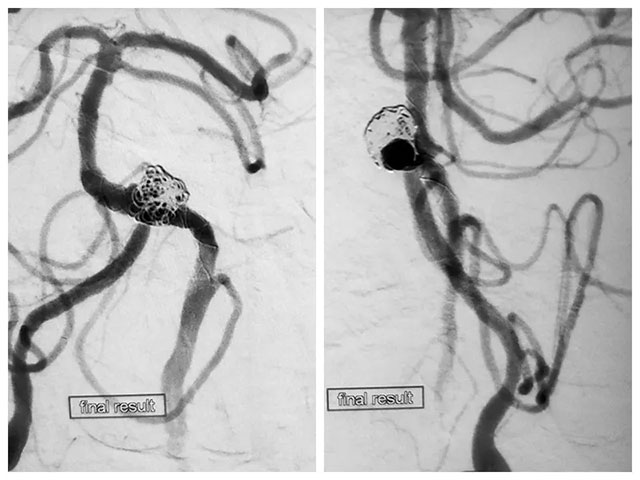

張琪博士在劉春醫(yī)生、周林華醫(yī)生協(xié)助下成功為患者進(jìn)行了左側(cè)椎動(dòng)脈閉塞開(kāi)通術(shù)、左側(cè)椎動(dòng)脈夾層動(dòng)脈瘤支架輔助彈簧圈栓塞術(shù)。

先向瘤體內(nèi)稀疏填入一枚彈簧圈,隨后釋放支架至覆蓋瘤頸,隨后通過(guò)支架網(wǎng)孔繼續(xù)向瘤腔內(nèi)填入數(shù)枚彈簧圈,再次造影見(jiàn)大部分瘤體不顯影。但子瘤內(nèi)仍可見(jiàn)少量血流,通過(guò)支架導(dǎo)管再次釋放一枚支架覆蓋瘤頸,再次造影后見(jiàn)動(dòng)脈瘤無(wú)顯影,撤出系統(tǒng)后行血管造影,未見(jiàn)血栓形成,CT檢查無(wú)出血。

DSA造影手術(shù)、左側(cè)椎動(dòng)脈閉塞開(kāi)通手術(shù)、支架輔助彈簧圈栓塞手術(shù)處理夾層動(dòng)脈瘤和子瘤,這位病患先后進(jìn)行了四次手術(shù),歷時(shí)近12小時(shí),最終完成血管內(nèi)重建性治療。

▲ 術(shù)后造影